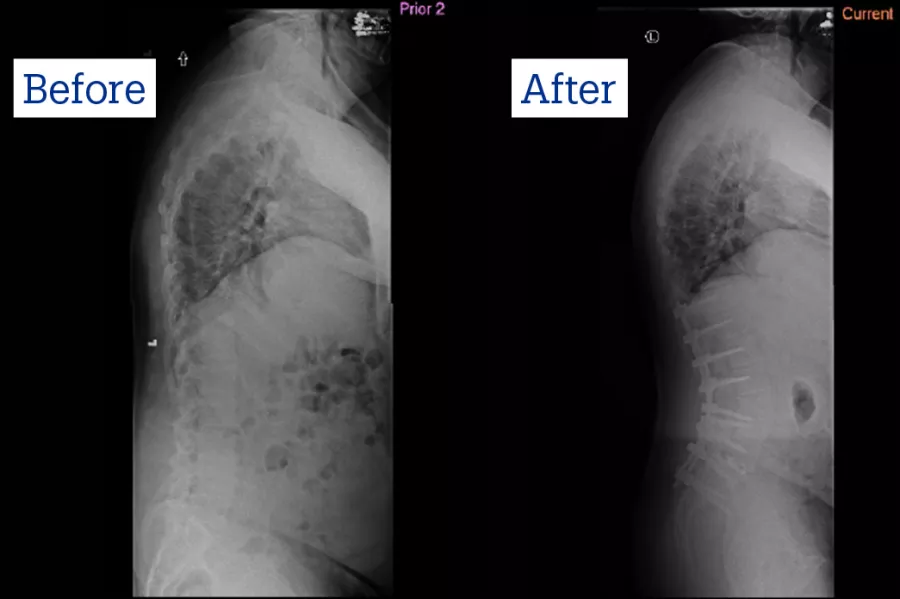

Peter Bradford couldn’t believe his eyes when Ron Riesenburger, MD, showed him an X-ray of his spine.

The discs in Peter’s spine were collapsing and degenerating, which was the reason he was in tremendous pain, hunched over and leaning to the left, unable to walk 100 feet to his mailbox.

“It was bad; it looked like my spine was tipping over, and one of the vertebrae was coming out of place,” said Peter. His wife Trisha added that he was “bent over like an L” and spent his days in a recliner, unable to do anything but watch TV.

He was diagnosed with kyphosis, where the spine curves outward and severe kyphoscoliosis, which causes spinal abnormalities. Peter would need major spine surgery that couldn’t be done in Norwood.

Peter underwent the surgery in May of 2020, during the height of COVID, and remained in the Intensive Care Unit for 6 days. To straighten and restore the normal curvature of the spine, Dr. Riesenburger fused vertebrae, securing the spine with rods and screws.

“The gist of it is, it’s tremendous (amount of) hardware; 3 quarters of my back is rods,” said Peter, now 71. “I can’t bend over; my posture is always correct.”